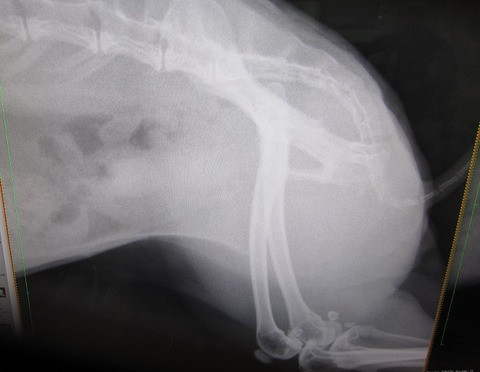

まさかあの9mmの石が出るとは…何で出たんかとかお話の前に、

まずは、石ゼロを確定させるべく早々レントゲンへ。

向かって左が今回、右がこないだ。

光の加減で膀胱全体が白っぽく見えますが石はありませんっ

石はありませんっ